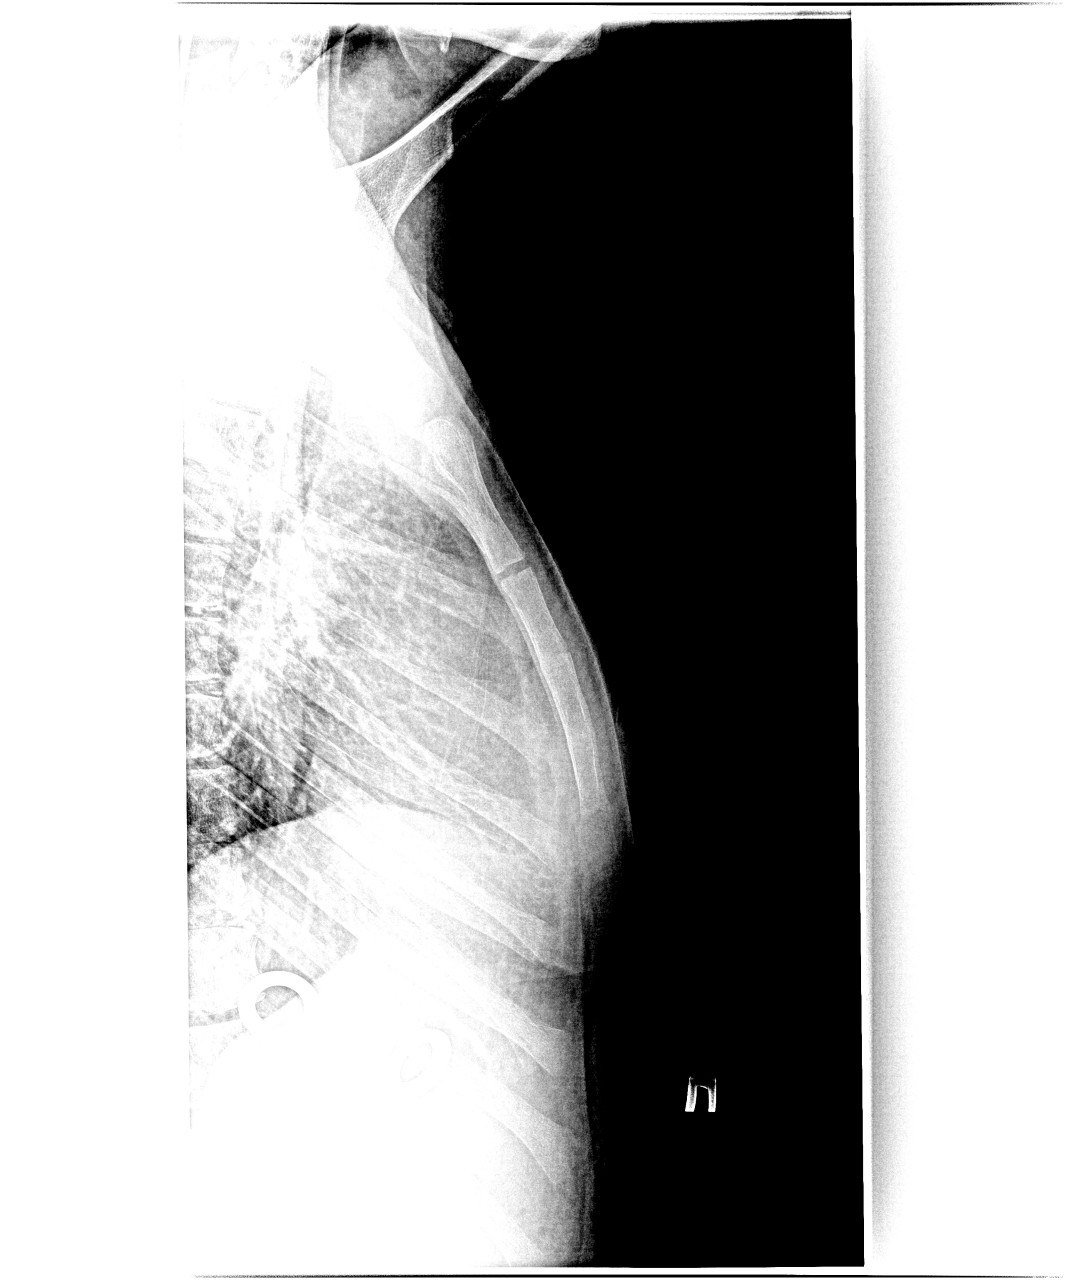

Нет, теперь кажется что всё-таки есть перелом головки луча (латер.)

а вторая проекция? И кружок на 2 см выше надо нарисовать, чтоб головку луча сломанную обвести

Ж12. Удар с ноги вчера. Из примечательного - с 2012 г. второй перелом с таким смещением (прошлый - женщина после высотки)

Похожие травмы часты при ударе об руль при ДТП. При резком торможении

Так где там перелом, чисто грудина?

просто редкий снимок в копилку